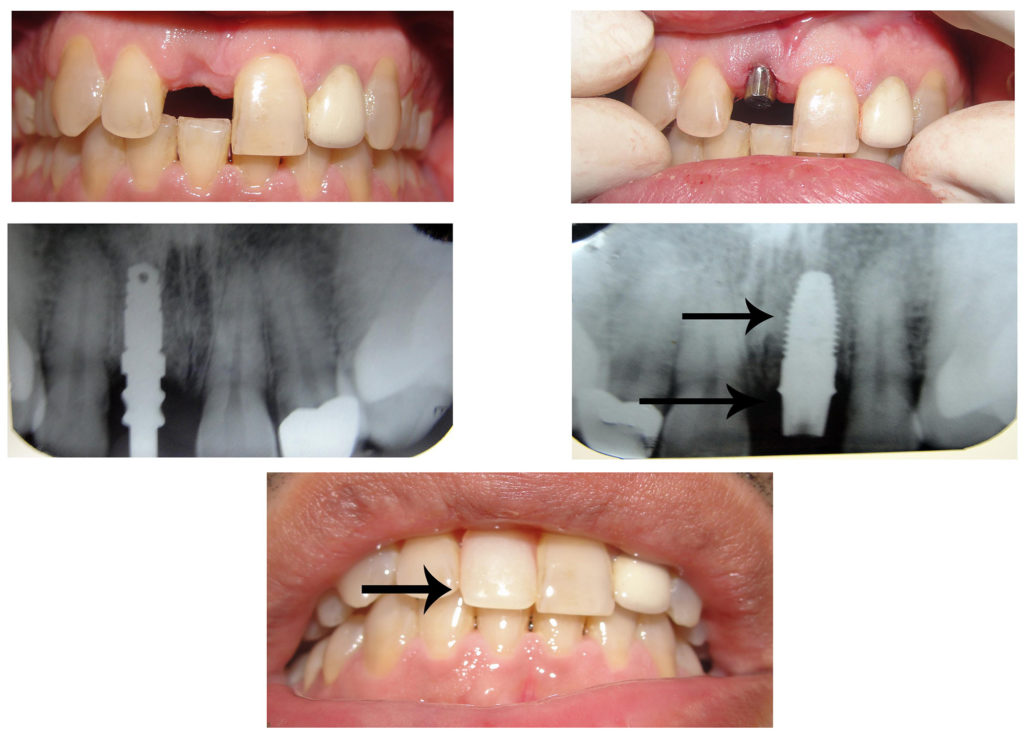

Case 1:

Patient: Kaushik, 28 yrs. Front single tooth missing, replaced with implant and immediate tooth replacement with 3-4 days.